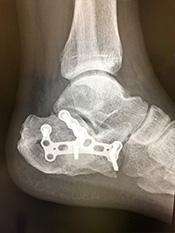

足関節骨折(足首の骨折)

転倒/転落時に足をねじった場合に生じる骨折です。

多少のずれでも、骨がつくのが遅れたり、足首の障害が残ることの可能性が高い骨折のため手術を選択されることが多いものです。

• 画像:足関節骨折

(術前)

(術後)

• 画像:骨折観血的手術(足)プレート固定、テンションバンド

骨折観血的手術(足)

プレート固定、テンションバンド

• 画像:骨折観血的手術(足)プレート固定

プレート固定